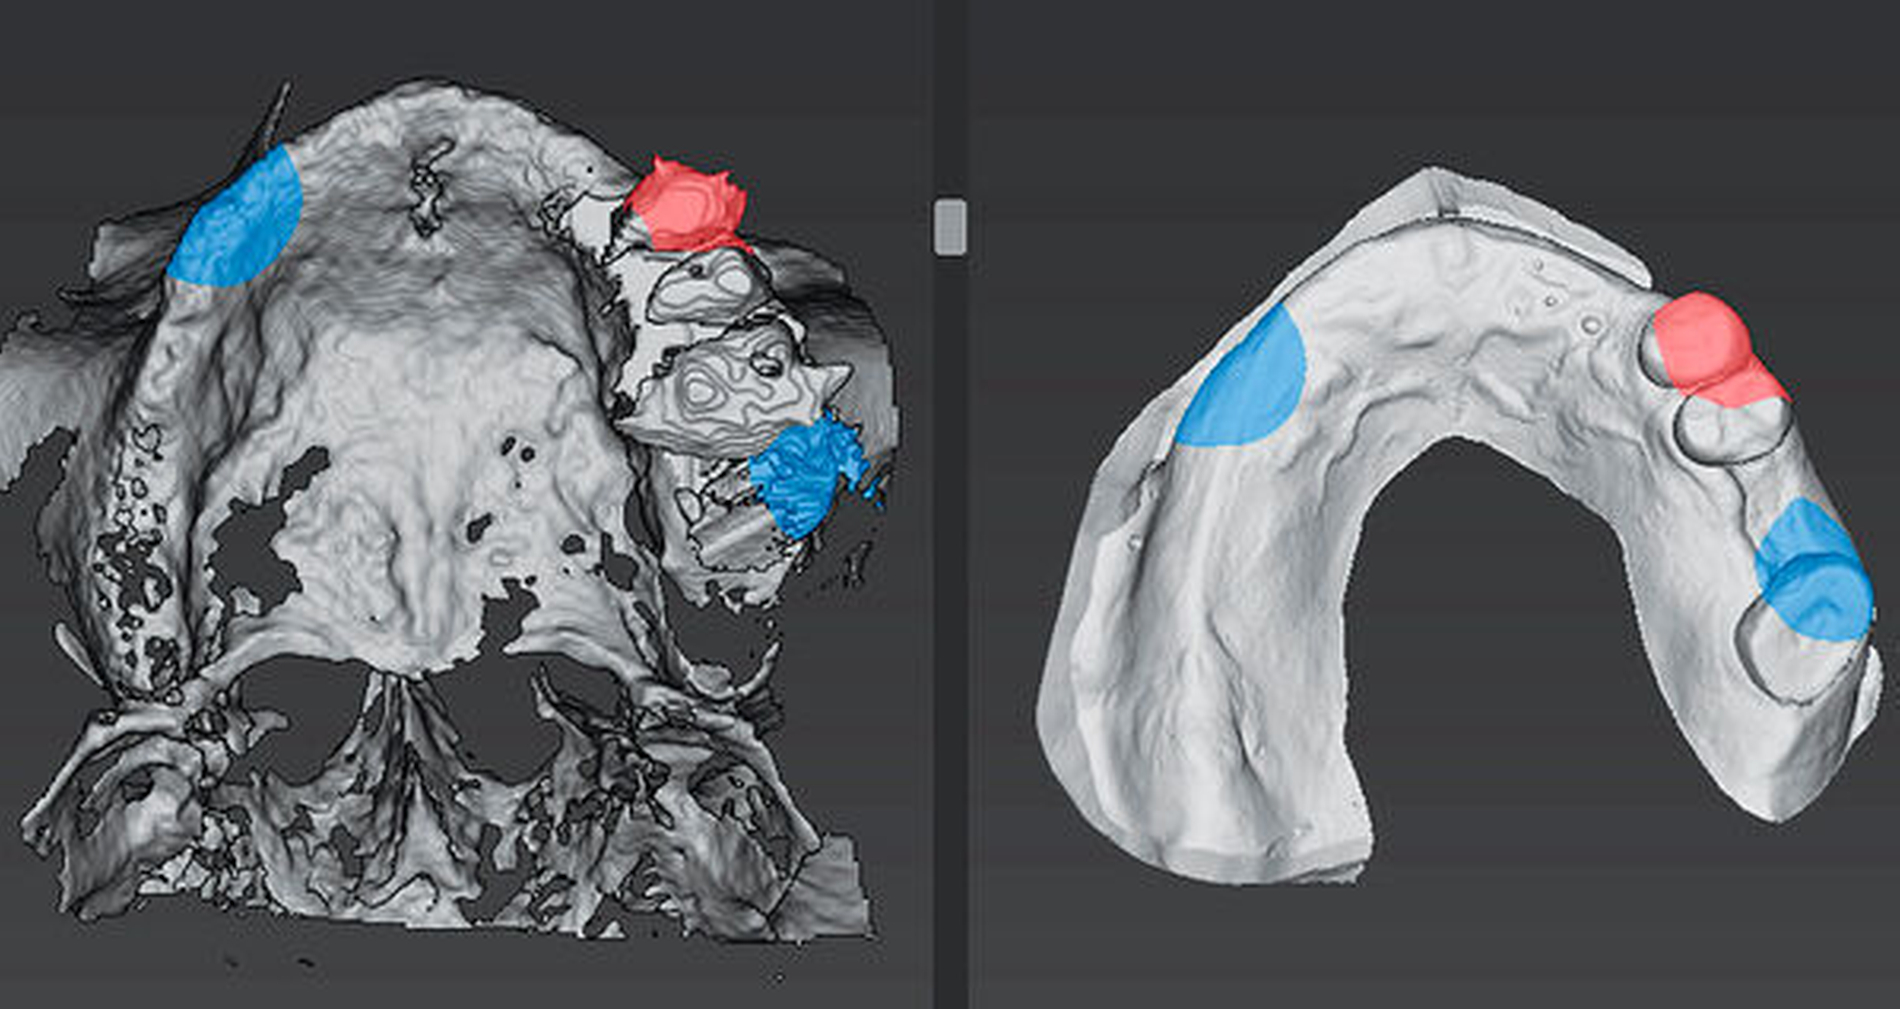

Soll eine OP-Schablone digital designt werden, muss zunächst ein Oberflächendatensatz der teil- oder unbezahnten Situation gematcht werden. Da auf dieser Oberfläche die Schablone gestaltet wird, mit der die Übertragung der virtuellen Planung erfolgt, ist es an dieser Stelle besonders wichtig, dass das Matchen hochpräzise möglich ist. Sehr unterschiedlich und zum Teil schwierig kann die Umsetzung bei einer geplanten Sofortimplantation sein. Wenn an der zukünftigen Implantatposition noch Zähne vorhanden sind, die erst intraoperativ entfernt werden, kann die optimale Positionierung der Bohrhülsen oft schwierig sein. Selbstverständlich lässt sich auch der Scan einer späteren prothetischen Versorgung mit den radiologischen Bilddaten matchen, um so die Implantatposition und die Implantatachse bestmöglich auf die angestrebte Versorgung auszurichten. Mit dieser deutlich alltagstauglicheren Methode wird aus der reinen Knochendarstellung des DVTs tatsächlich eine echte bidirektionale Visualisierung auch der prothetischen Versorgung.

Die entsprechenden Planungssysteme ermöglichen heute den Import der standardisierten DICOM-Daten. Ebenso auch der STL-Oberflächendaten des Scans. Mit den Systemen lässt sich der radiologische Bilddatensatz als Oberflächendarstellung „segmentieren“. Zusätzlich zu den Scans lassen sich auch die virtuelle Zahnaufstellung einblenden und Risikostrukturen (Nerv) visualisieren. Nach der dreidimensionalen Planung von Implantatposition und -dimension erfolgt die Planung der Bohrschablone am Computer. Dies geschieht meist teilautomatisiert. Ein nicht zu unterschätzender Aspekt bei der Planung der Schablone ist die Auswahl des Hülsensystems mit den entsprechenden Implantatbohrern. Nach der Planung werden die Daten der Schablone exportiert und im Zahnlabor oder im 3-D-Drucker hergestellt. Damit bieten viele Systeme – Hersteller-unabhängig – heute an, vor Ort in der eigenen Praxis an einfachen Computern eine entsprechende Planung herzustellen. Mit der Verfügbarkeit der 3-D-Drucker ist auch die Erstellung einer eigenen Schablone vor Ort durchaus möglich.